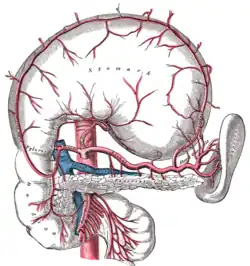

Vascularização do baço

A artéria esplênica (ou lienal) faz a vascularização do baço, que é ricamente vascularizado. É o ramo esquerdo do tronco celíaco, que sai da porção abdominal da artéria aorta.

A artéria celíaca e seus ramos.

Secção transversa do baço, mostrando seu tecido trabecular, a veia esplênica e suas tributárias.

Secção transversa do baço, mostrando a distribuição da artéria esplênica e seus ramos.